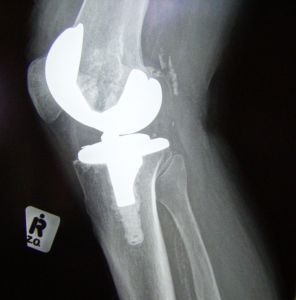

A total knee replacement (TKR) is usually done as the surgical treatment option for advanced osteoarthritis of the knee joint.During the surgery, the knee joint is replaced with artificial material. The knee joint is made up of the femur (thigh bone), the tibia (shin bone), the patella (knee cap) and cartilage (usually worn out because of OA).The end of the femur is removed and replaced with a metal surface and the top of the tibia is removed and replaced with a plastic piece that has a metal stem. If the knee cap has also degenerated, a plastic piece may be added to the back surface to create a smoother joint surface.